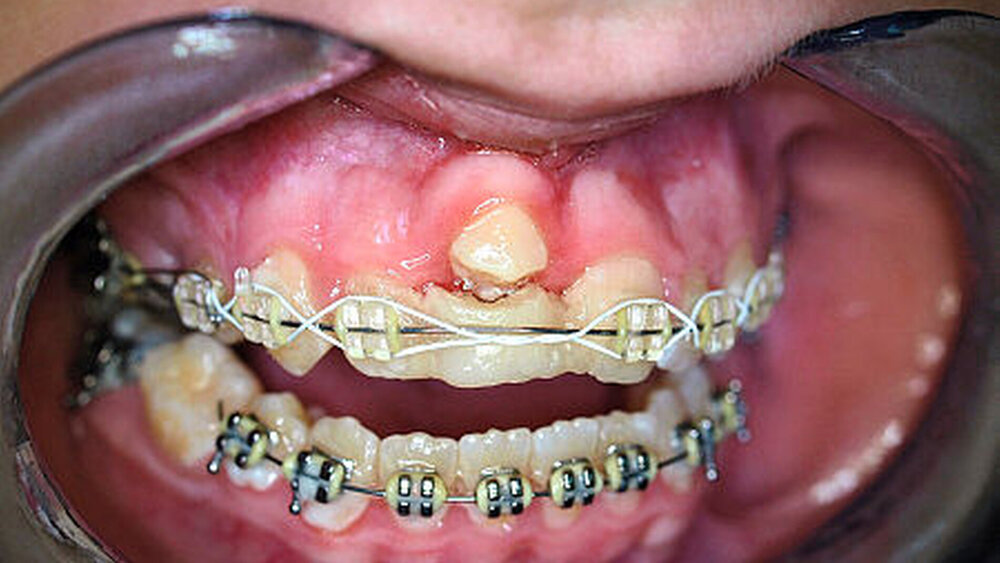

Abbildung 4a stellt einen weiteren Fall einer posttraumatischen Ankylose nach Avulsion und Replantation des Zahnes 11 mit rund 60-minütiger Trockenlagerungszeit bei einem zwölfjährigen Jungen vor, bei dem es inzwischen (pubertärer Wachstumsschub) zu einem erheblichen vertikalen Wachstumsdefizit des betroffenen Kieferabschnitts in regio 11 gekommen ist: Das Weichteildefizit im Vergleich zum gesunden Nachbarzahn beträgt etwa 3 mm. Es zeichnet sich bereits ab, dass eine spätere implantologische Versorgung des Patienten im Alter von etwa 18 Jahren nur mit hohem chirurgischem Aufwand möglich sein wird.

Ein besonderer Stellenwert bei der Therapie dieses Krankheitsbildes kommt der autogenen Zahntransplantation zu, die das vorhandene Knochendefizit bis zum Erreichen des Wachstumsabschlusses mit hoher Sicherheit ( 90 Prozent) wieder aufholen kann [Pohl, 2008; Andreassen, JO 2009; Nolte, 2011; Tschammler, 2015]. Die Abbildungen 4b und 4c zeigen die vollständige klinische Rehabilitation nach autogener Prämolaren-Transplantation mit kieferorthopädischer Einstellung des Zahnes und nachfolgendem kieferorthopädischem Lückenschluss. Die mittleren Zehn-Jahres-Überlebensraten dieser chirurgischen Methode liegen bei 90 Prozent [Andreasen, 2009]. Wichtig für den zuverlässigen Erfolg der Methode ist das Zeitfenster für die Transplantation der Prämolaren, bei denen das Wurzelwachstum zwei Drittel bis drei Viertel der Wurzellänge betragen sollte. Insofern sollten sich Zahnärzte mit dieser Methode vertraut machen, um Patienten und Eltern in derartigen Fällen aufklären zu können.